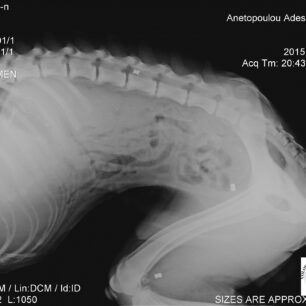

Το ζώο ήταν τόσο εξασθενημένο, τόσο υποσιτισμένο και αφυδατωμένο που σε κάθε δύο βήματα έπεφτε. Σηκωνότανε με δυσκολία ενώ από την μύτη του έσταζε αίμα. Τελικά η κοπέλα με τη βοήθεια ενός ακόμα ευαίσθητου νεαρού του κτηνιάτρου Φιλήμονα Διαμαντή κατάφερε να το πιάσει. Το σκυλί μεταφέρθηκε στο κτηνιατρείο του κ. Διαμαντή και οι ακτινογραφίες έδειξαν ότι στο κορμί του έφερε και τρία σφαιρίδια από αεροβόλο όπλο.

Το εκπληκτικότερο όμως, που είναι και ο λόγος για τον οποίο γράφω αυτό το άρθρο, είναι ότι στις ακτινογραφίες που του έγιναν με έκπληξη είδαμε να φαίνονται οι σκιές από τρία μικρά βόλια αεροβόλου όπλου σε διάφορα σημεία του σώματος του.